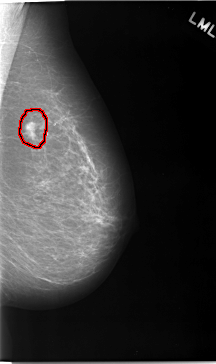

C_0046_1.LEFT_MLO

LEFT_MLO LINES 5824 PIXELS_PER_LINE 3456 BITS_PER_PIXEL 12 RESOLUTION 50 OVERLAY

FILE: C_0046_1.LEFT_MLO.OVERLAY

TOTAL_ABNORMALITIES 1

ABNORMALITY 1

LESION_TYPE MASS SHAPE LOBULATED MARGINS SPICULATED

ASSESSMENT 5

SUBTLETY 5

PATHOLOGY MALIGNANT

TOTAL_OUTLINES 1

BOUNDARY